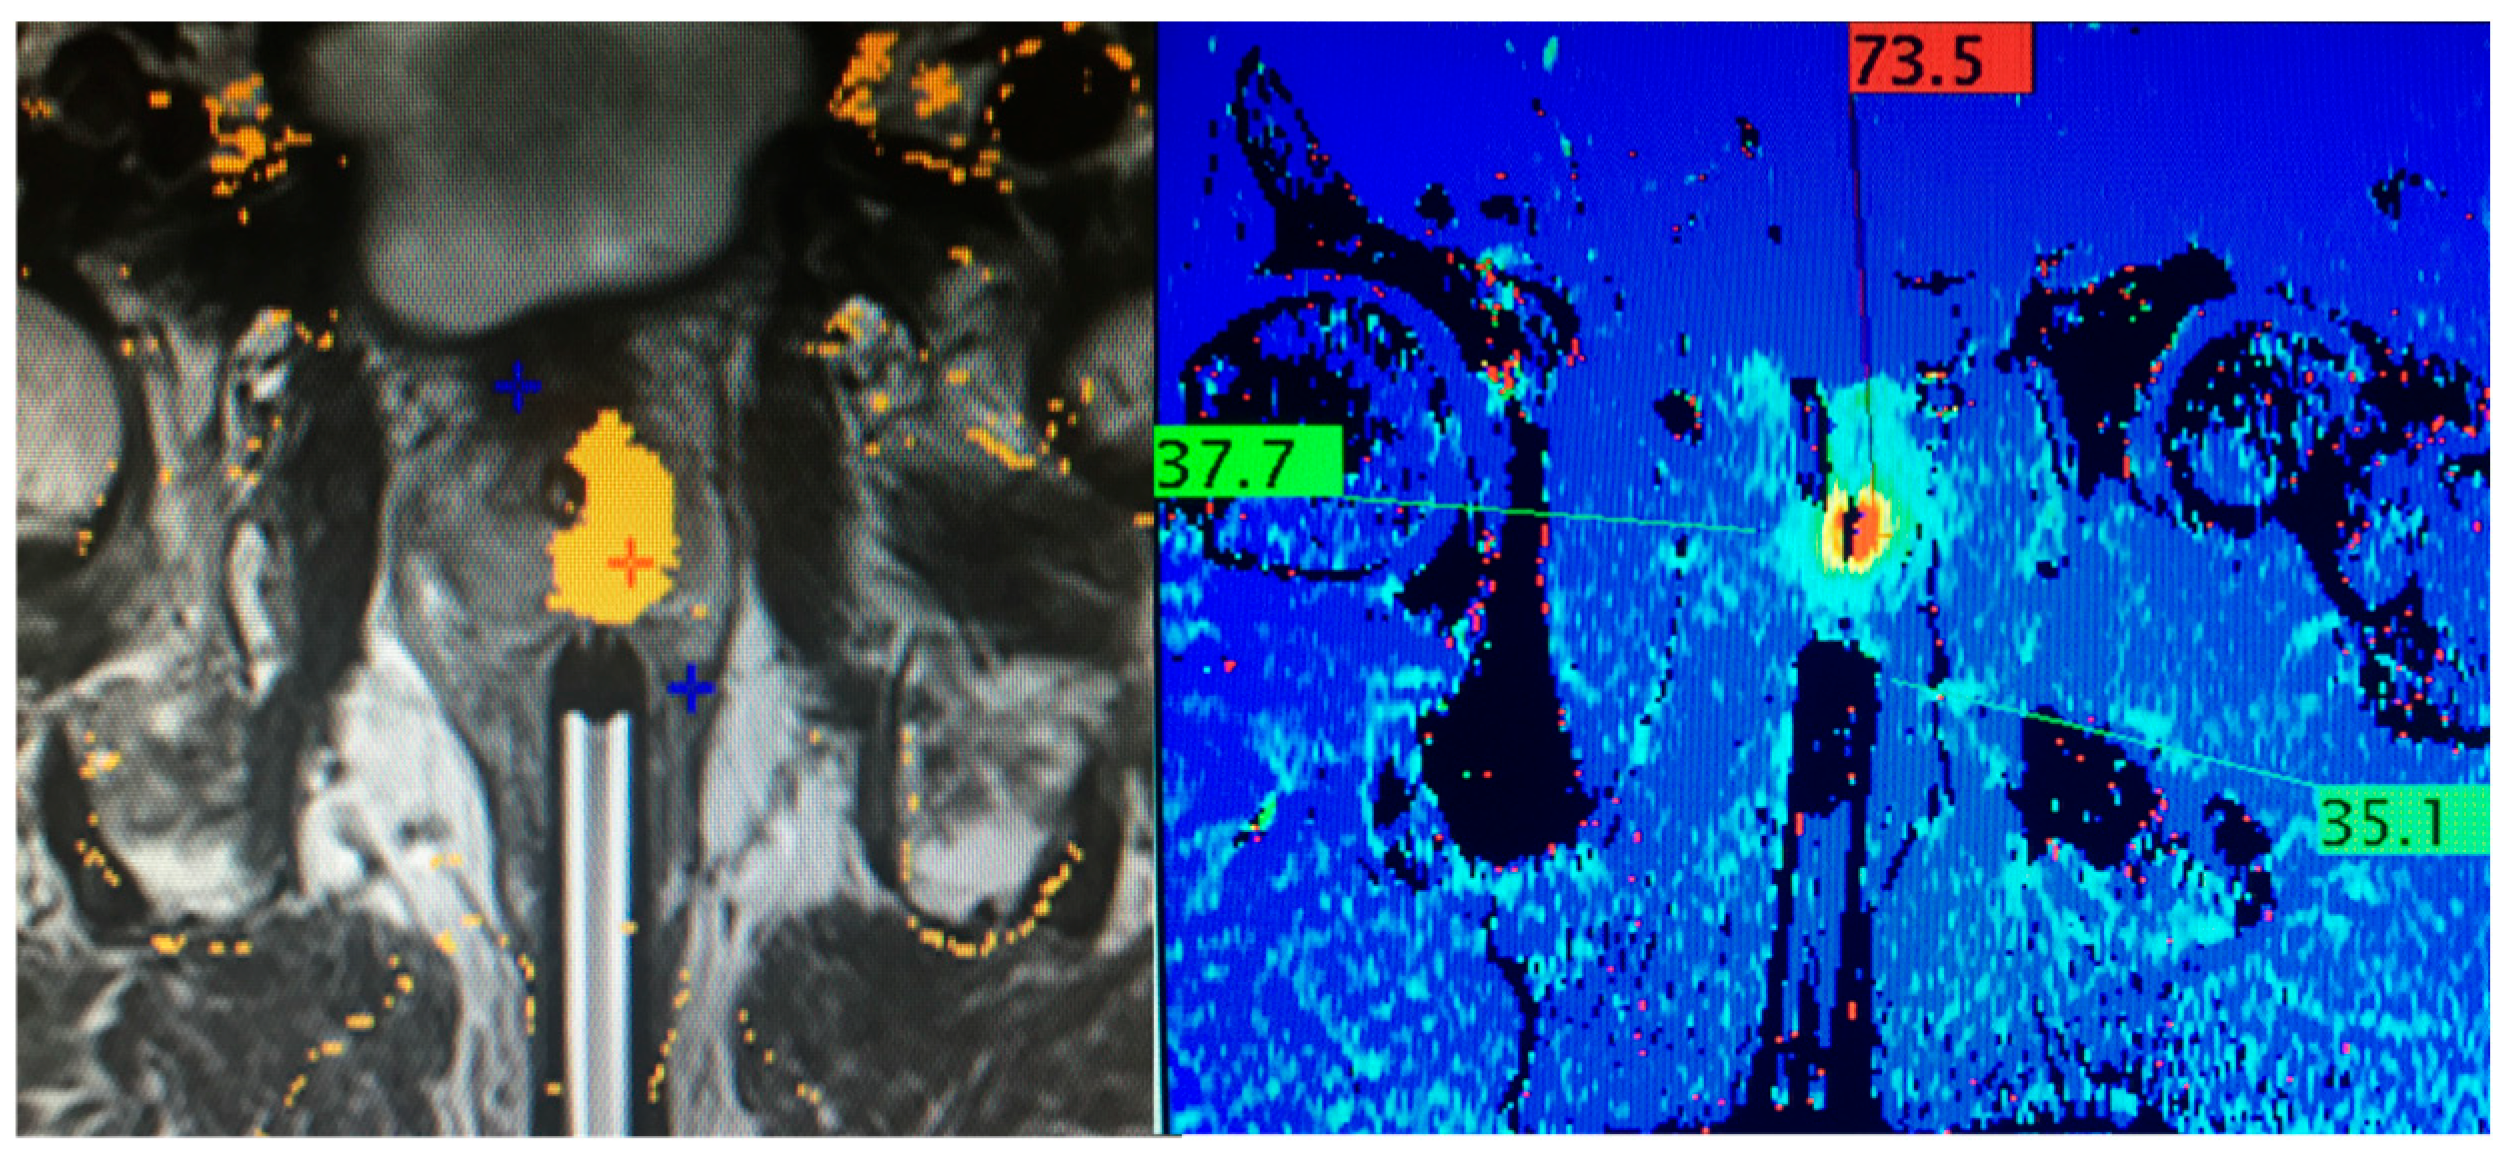

- Manenti, G.; Perretta, T.; Calcagni, A.; Ferrari, D.; Ryan, C.P.; Fraioli, F.; Meucci, R.; Malizia, A.; Iacovelli, V.; Agrò, E.F.; et al. 3-T MRI and clinical validation of ultrasound-guided transperineal laser ablation of benign prostatic hyperplasia. Eur. Radiol. Exp. 2021, 5, 41. [Google Scholar] [CrossRef] [PubMed]